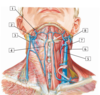

A

16

2

2 - retromandibular vein

Q

A

18

4

4 - anterior jugular vein

Q

A

20

6

6 - internal jugular vein

#7

30

#8 - transverse cervical artery

#9

31

#1 - superficia temporal artery

#2

33

#3 - internal carotid artery

#4

35

#5 - common carotid artery

#6

37

#7 - ascending pharyngeal artery

#8

39

#9 - facial artery

#10

41